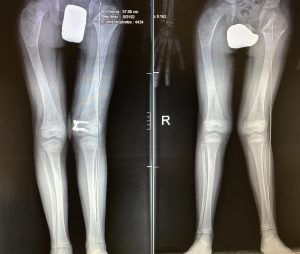

In